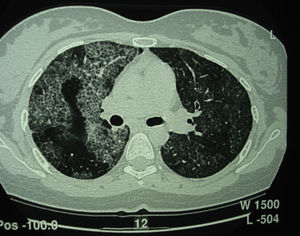

La proteinosis alveolar pulmonar (PAP) es una enfermedad rara que fue descrita por primera vez en el año 19581. Se caracteriza por la acumulación del material lipoproteináceo del surfactante en los espacios alveolares y bronquiolos terminales, lo que puede llegar a producir alteraciones en el intercambio gaseoso2 (fig. 1). Esta acumulación del surfactante es debida a una disminución en su aclaramiento por parte de los macrófagos alveolares, siendo característica la presencia de macrófagos alveolares con inclusiones de material fosfolipoproteico. Su incidencia estimada es de 0,2-0,4 casos por millón de personas/año, con una prevalencia de 3,7-6,2 personas/año3. Hasta el año 2002 se habían descrito en la literatura unos 410 casos4.

Tomografía computarizada de alta resolución (TACAR) de un pacientes con proteinosis alveolar pulmonar (PAP) que muestra las características clásicas de los septos interlobulillares engrosados contra un fondo de opacidades en vidrio esmerilado, dando la típica una apariencia de crazy paving.